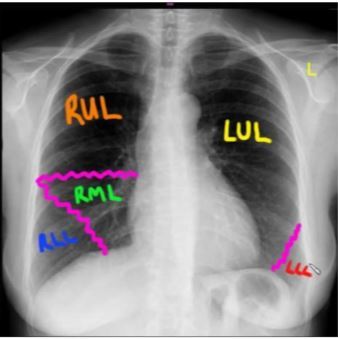

Try and draw where the different lung lobes are

Add photo